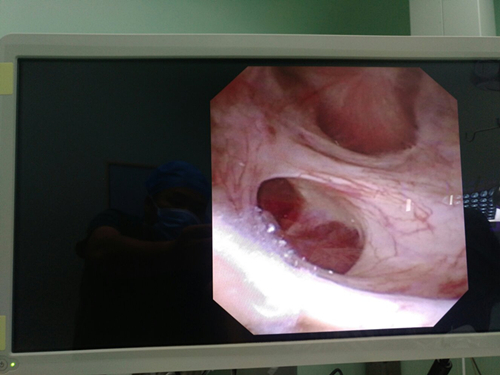

日前,我院泌尿外科在麻醉科、手术室配合下成功开展电子输尿管软镜下钬激光碎石术。在专业医护团队的共同努力及精心治疗下,患有肾结石或输尿管上段结石的患者治疗效果更理想。电子输尿管软镜碎石取石术是我院泌尿外科继体外冲击波碎石术、输尿管硬镜碎石取石术之后在尿路结石微创治疗方面开展的又一项新技术。该技术只需通过患者的自然腔道,利用纤细可弯曲的软镜镜体到达输尿管上段、肾盂及肾盏,结合钬激光及套石篮行碎石、取石治疗,是目前治疗上尿路结石的理想手段,具有微创、安全、可靠等优点。电子输尿管软镜术除了用于治疗尿路结石,还可应用于泌尿外科的以下领域:1、上尿路上皮肿瘤的诊断和腔内治疗;2、不明原因血尿的病因诊断。

电子输尿管软镜下检查和碎石治疗的开展,标志着我院泌尿外科在微创泌尿外科领域又迈上一个新的台阶。